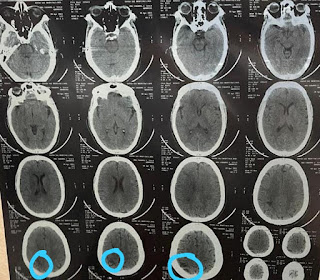

A 50 yr old female with LEFT SIDED HEMIPLEGIA WITH LEFT SIDED UMN TYPE FACIAL PALSY (COMPLETE HEMIPLEGIA) probably due to an ISCHEMIC STROKE caused by a cerebral THROMBUS in the MCA territory involving RIGHT SIDED INTERNAL CAPSULE with H/O HTN, DM.

CT BRAIN-